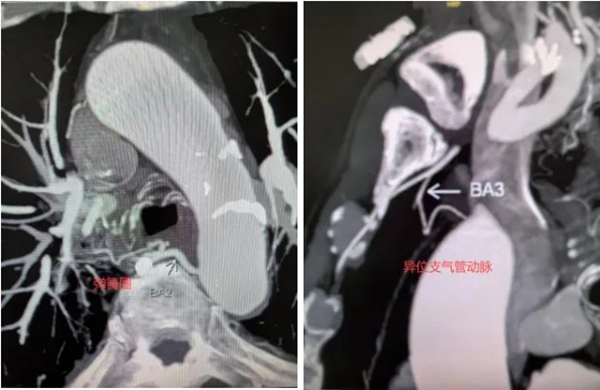

一位有既往结核病引起咯血病史的患者,五年前接受了支气管动脉栓塞术,患者因咳嗽伴痰中带血症状持续超过一个月,为获得进一步的治疗再次入院。入院后支气管动脉CTA检查显示,患者之前栓塞所用的弹簧圈如同拦路虎一般,横亘在右侧支气管与肋间动脉共干的主干近端。科室会诊讨论制定手术方案,提前预判手术难度,确定用微导管超选越过既往栓塞的弹簧圈,到达右侧支肋共干支气管动脉的远端分支进行有效栓塞。

征得患者家属同意后,李德志进行手术。他在助手默契配合下,经过多次尝试,在微导丝引导下成功将微导管超选越过既往栓塞的弹簧圈,顺利到达右侧支肋共干支气管动脉的远端分支,利用PVA微球和明胶颗粒,实现了有效的栓塞治疗。手术中,李德志对其他异常血管,包括左右共干支气管动脉、右侧胸廓内动脉发出的异位支气管动脉以及食管固有动脉分支进行了栓塞,最终取得了满意的临床治疗效果。患者顺利康复出院。